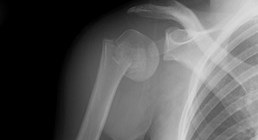

Motorcycle related injury

If you are me, and you show up for work in a sling, the first thing every single person that walks through the door asks is “um..is that motorcycle related?” […]